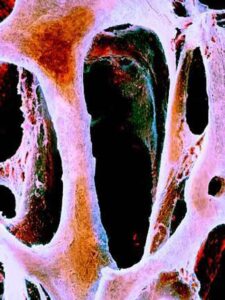

Il Silicio della birra che salva le ossa